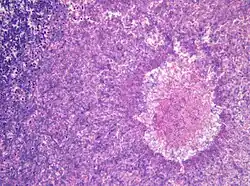

![]() Aspergillus niger. | |||||||||||||

Aspergillus Micheli, 1729 é um gênero de fungos que apresenta coloração branca ou amarelada com formação de pedúnculos e uma ponta colorida. São importantes agentes decompositores de alimentos. As espécies descritas com base em anamorfos que anteriormente se encontravam incluídas no género Eurotium foram transferidas para este género.[1]

Cerca de 16-20 espécies podem infectar o homem causando morte, sendo as mais comuns A. fumigatus, A. flavus e A. niger. As manifestações clínicas incluem micetomas (infecção subcutânea), reação de hipersensibilidade (aspergilose alérgica), aspergilose pulmonar (que pode conter aspergiloma e ser necrosante crônica) e sua forma mais letal: invasiva generalizada em imunocomprometidos. Injeções de posaconazol podem ser usados em casos de emergência.[2]